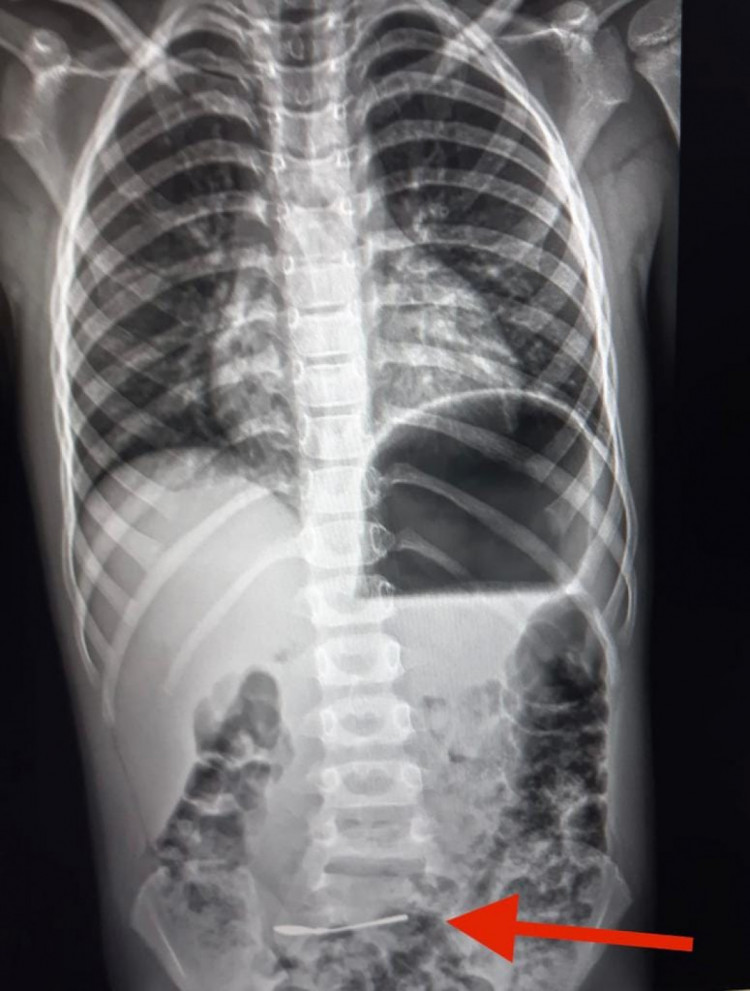

Так, у Харкові до обласної дитячої клінічної лікарні доправили 6-річну дитину зі срібною ложкою у кишківнику.